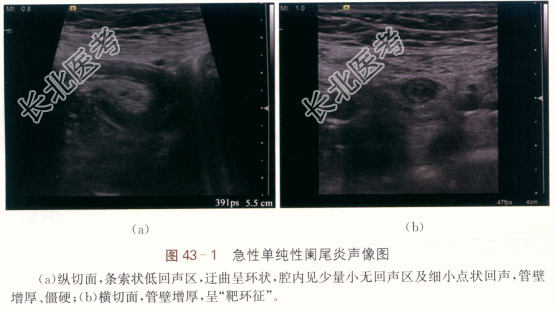

二、影像资料